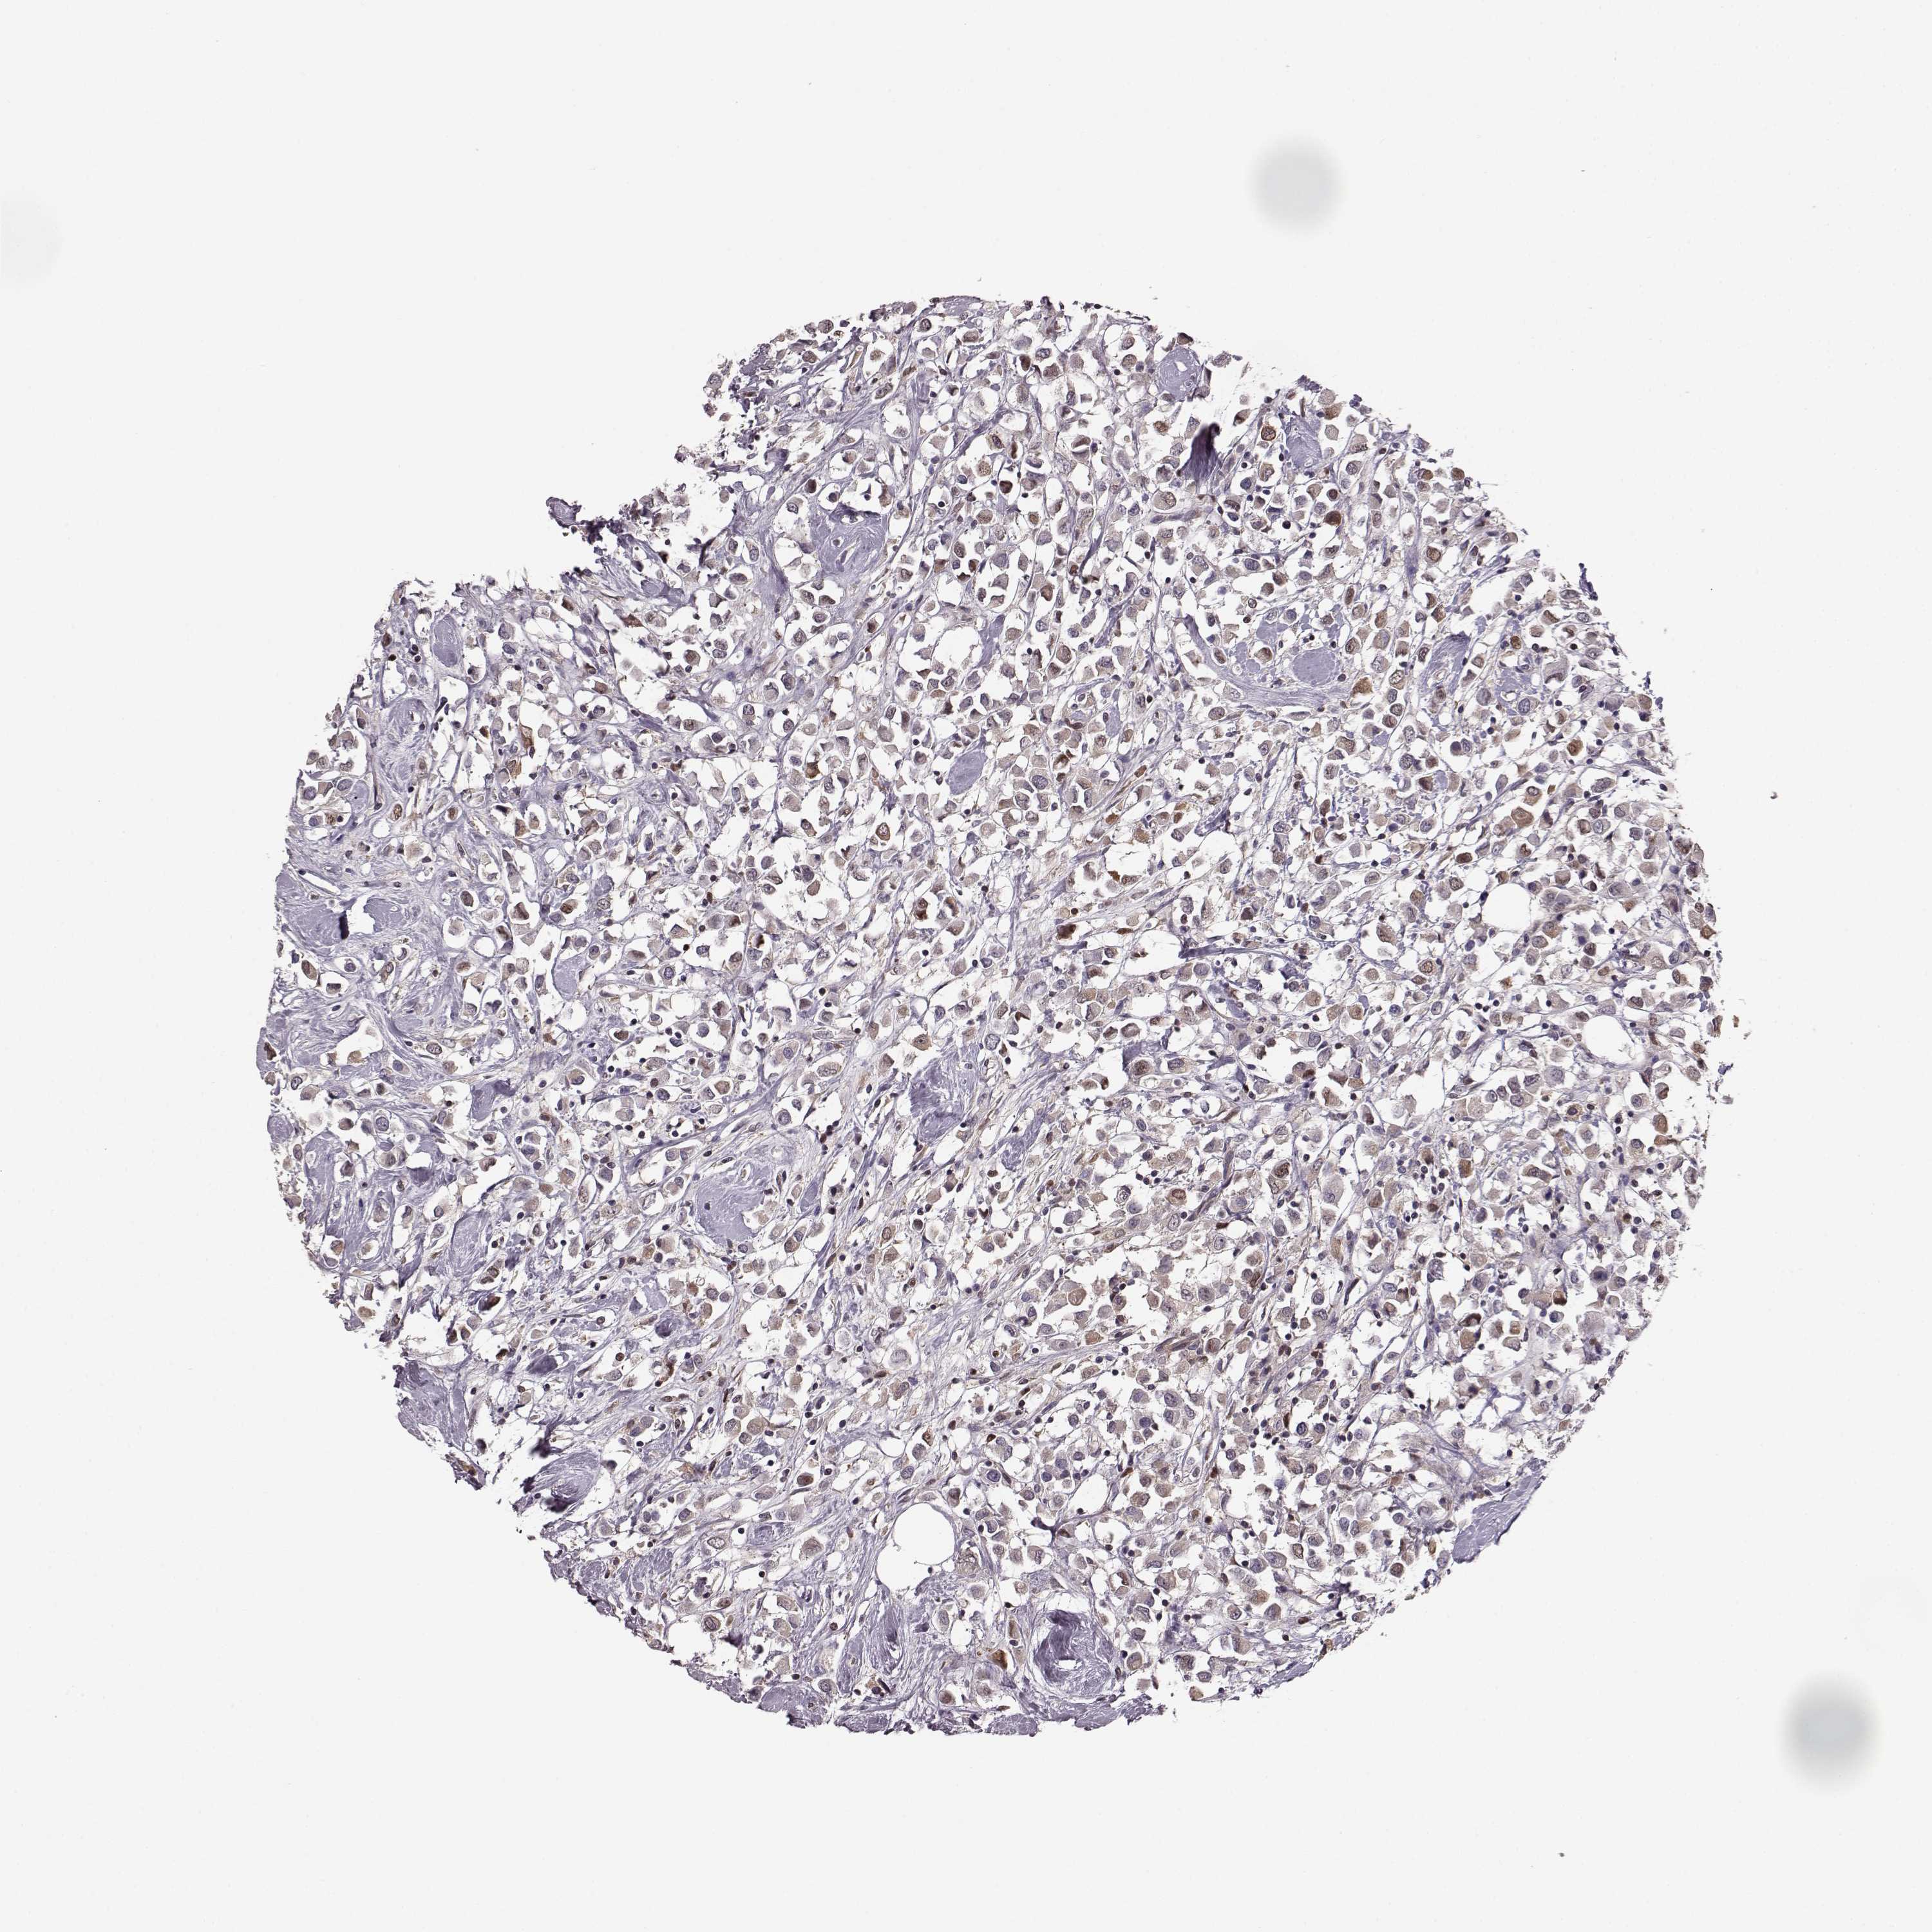

CANCER BREAST CANCER Show tissue menu

BRCA TCGA BRCA VALIDATION PROTEIN EXPRESSION